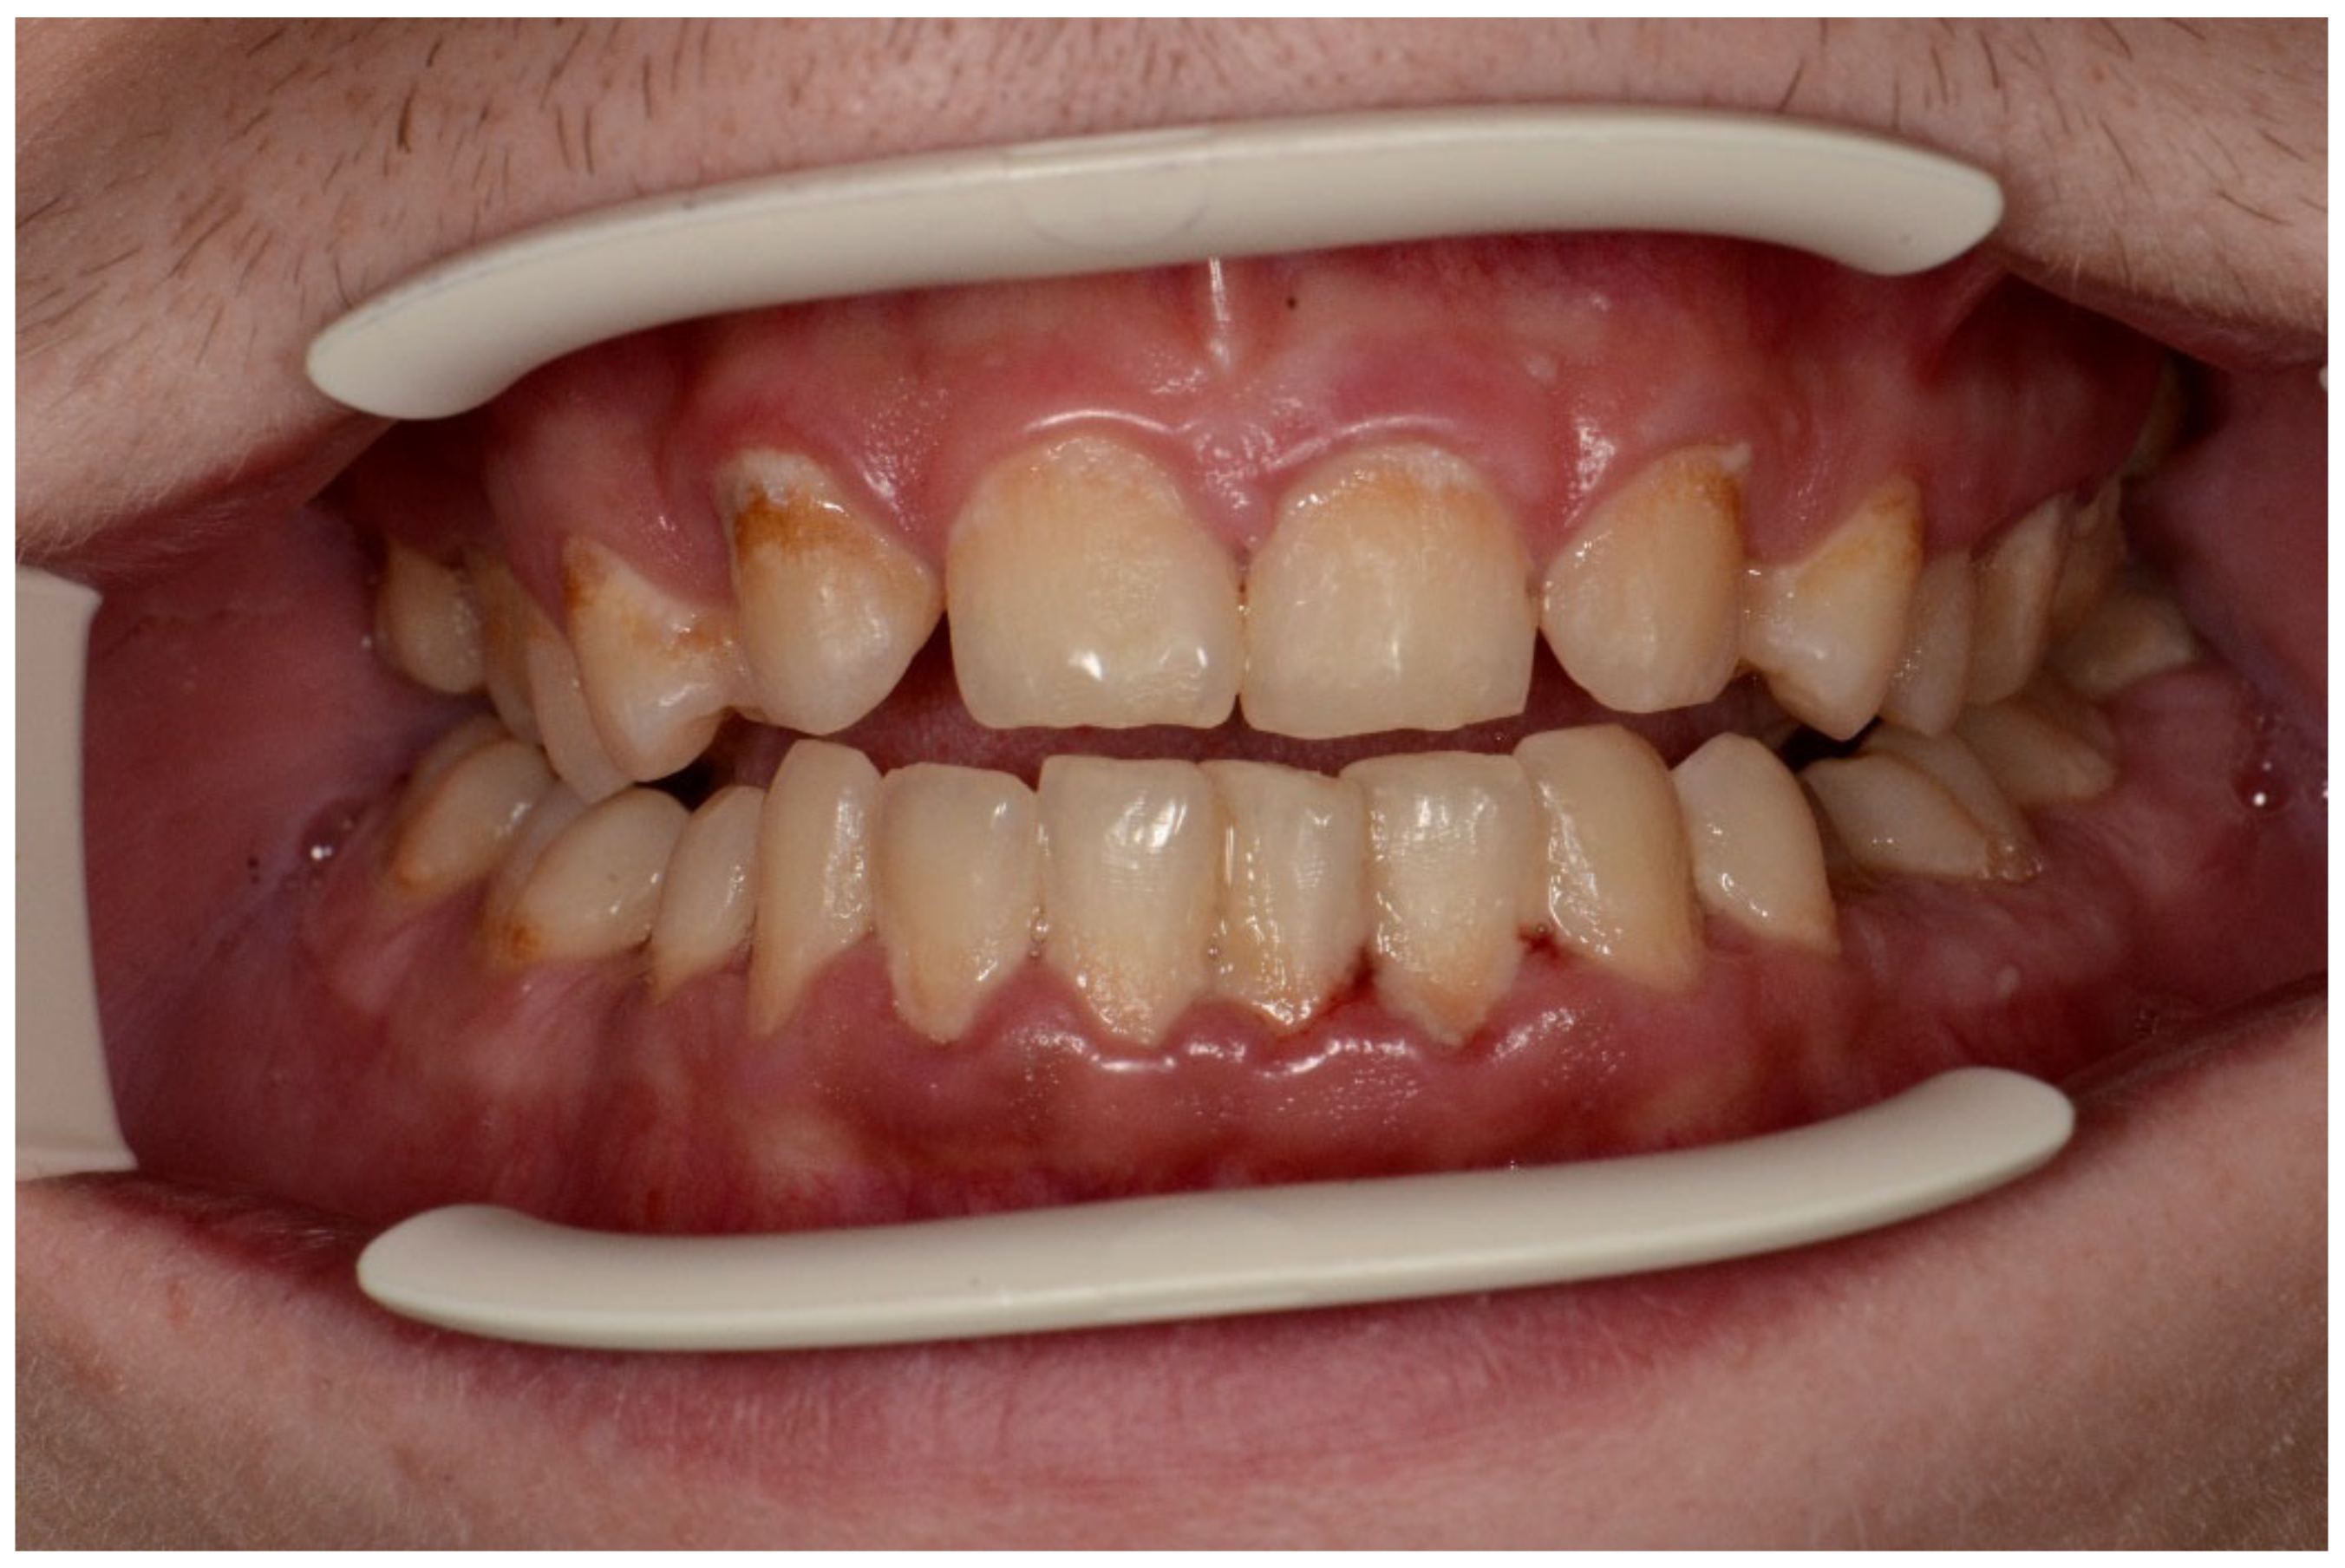

Examples of erosive defects occurring in the examined patients are presented in Figure 6, Figure 7a,b and Figure 8a–c.

Figure 7. (a,b) Man, 33 y.o. Advanced internal and external erosion. The patient reported regular vomiting and consumption of approximately 6 L of Coca-Cola per day over a period of more than 6 months—front teeth and upper arch.